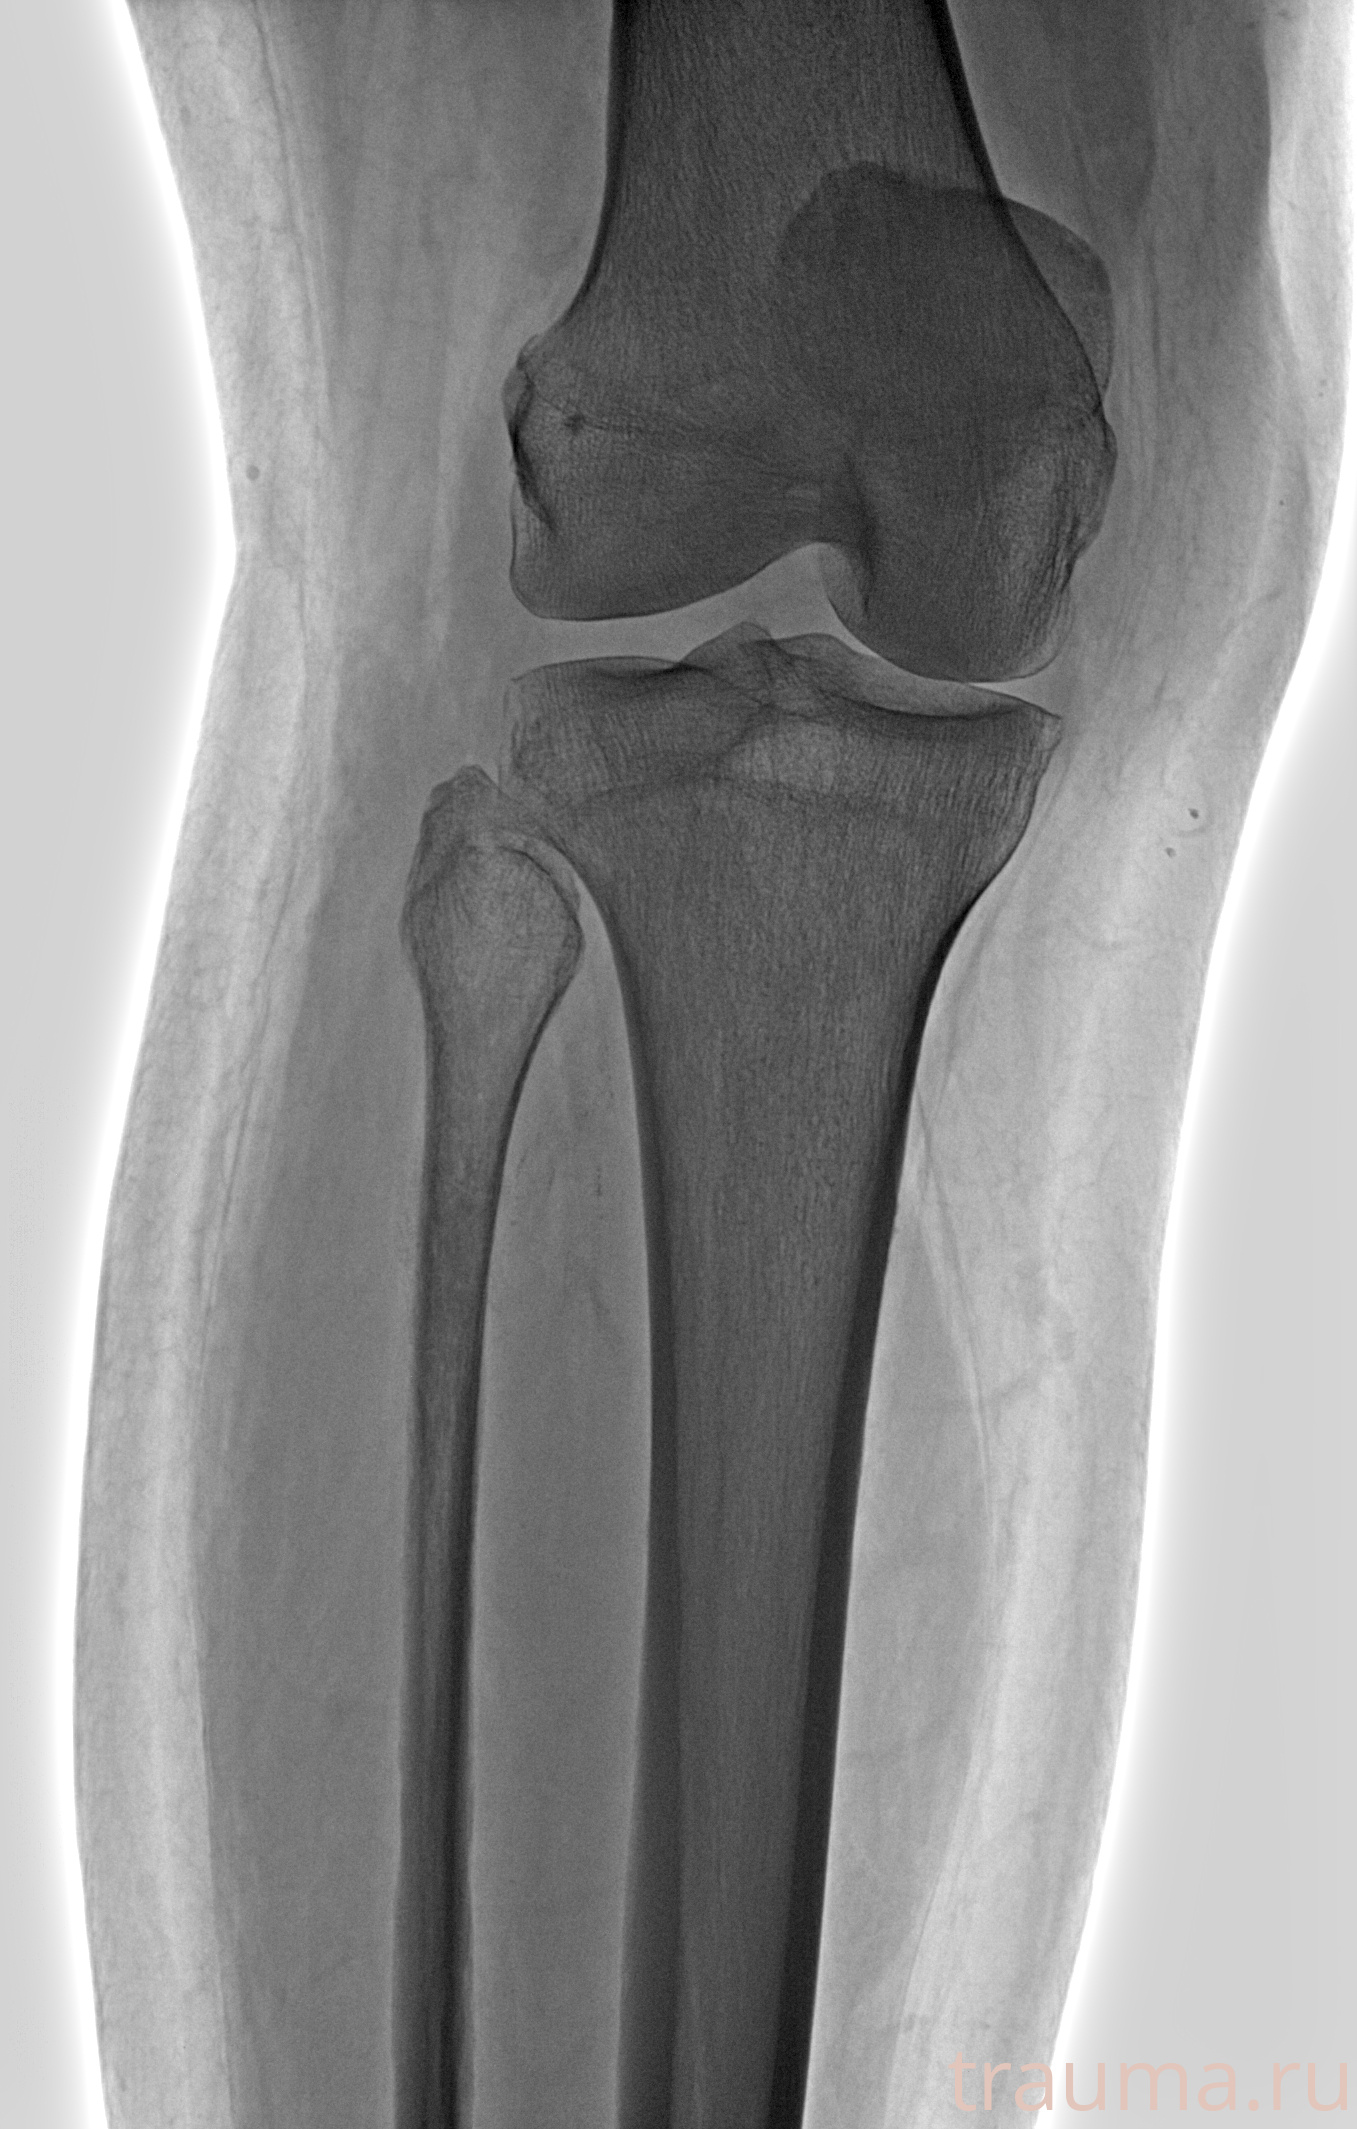

Рентгенограммы

Рентген на дому: по вашему адресу приезжает врач-рентгенолог, травматолог-ортопед с мобильным рентгеновским аппаратом, проводит диагностику травмы или заболевания, делает необходимые рентгенограммы, дает рекомендации по дальнейшему лечению. Получить качественные снимки в домашних условиях возможно благодаря уникальной методике, разработанной МосРентген Центром для института  Склифосовского